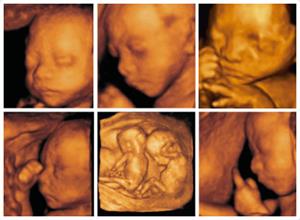

准妈妈在怀孕期间都会做b超来了解胎儿的发育状况,其中四维彩超为先进,通过立体彩色画面可以显示出胎儿身体各部分发育的情况,那么,什么时间做大排畸较好?安庆博爱医院专家为您介绍。

孕22周到孕28周是孕妇做4维彩超比较合适的时间,在这个时间段,胎儿已经发育完全,羊水适中,是排畸的比较适宜的时间,各孕妇应谨记4维彩超的时间,并适时检查,以免做过了做4维彩超的时间。

高清晰度的图像质量,能自动为胎儿进行宫内拍“写真”和动态录像,准妈妈们不再是仅仅感觉宝宝的呼吸和运动,而且可以亲眼目睹他们的一举一动和乖巧的面容。四维技术为众多准妈妈增添了安心和情趣。生个聪明健康的小宝宝,并且将宝宝的样子和动作制作成照片或VCD,让宝宝拥有完整的0岁相册,这已经不再是幻想。